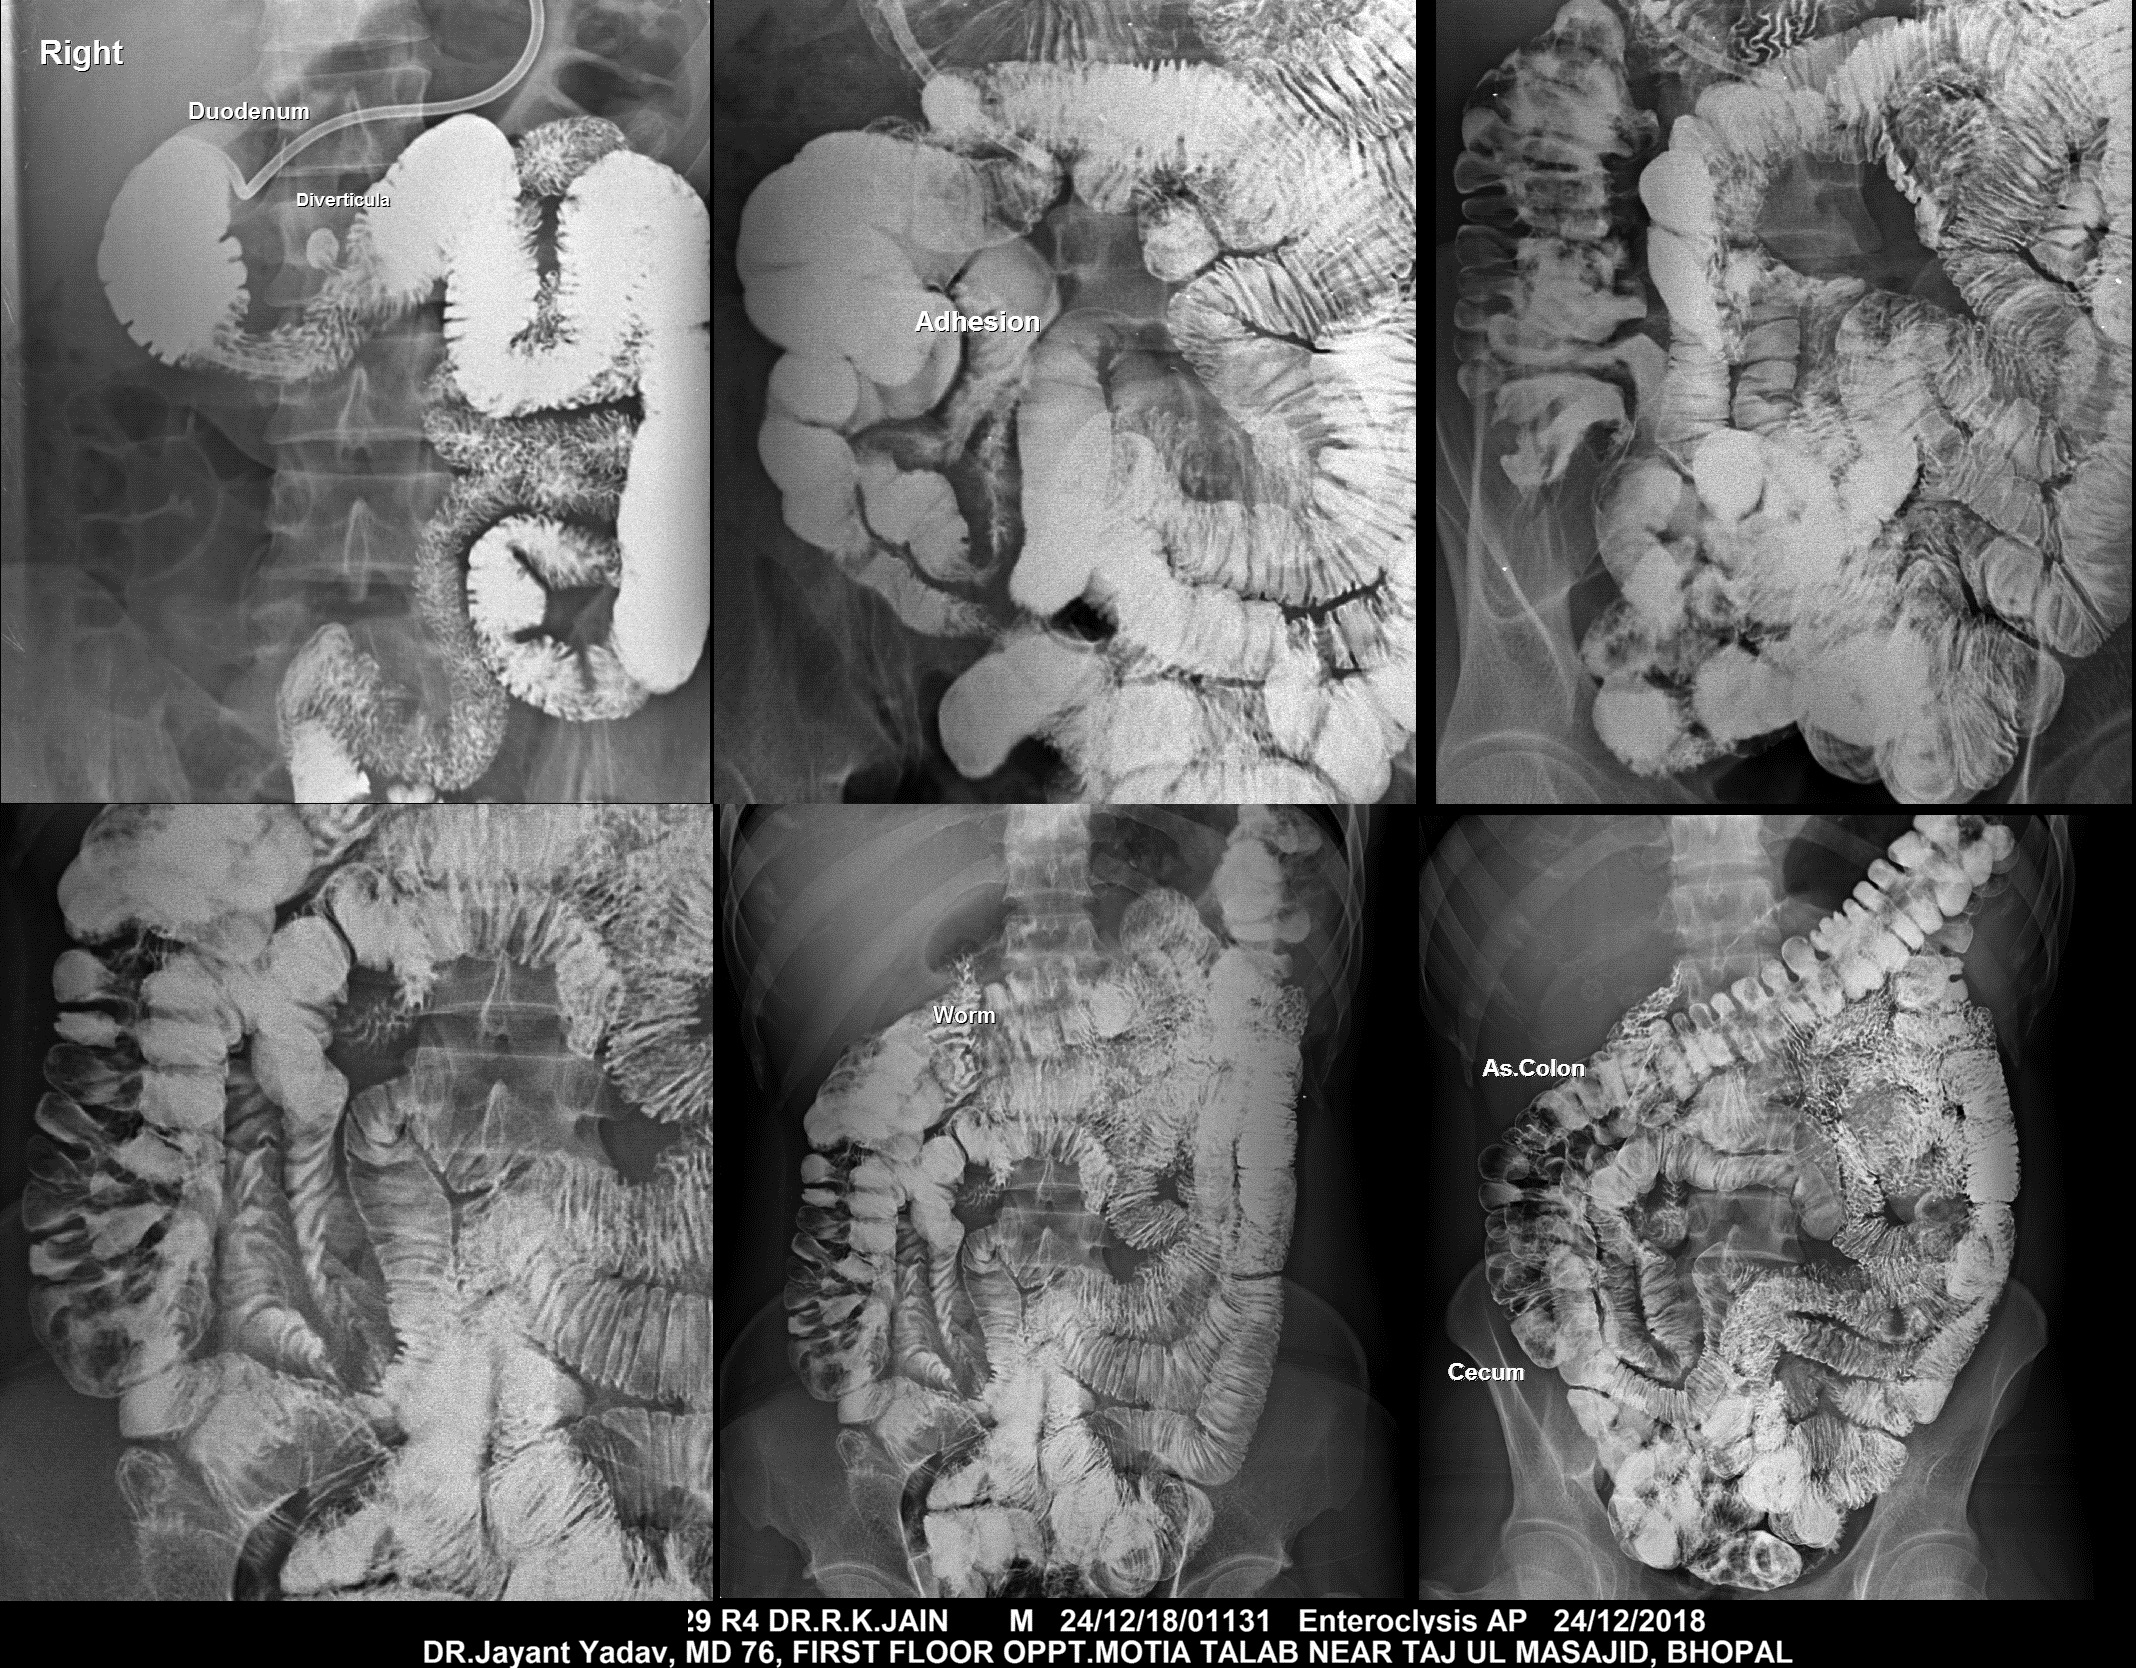

Section: ENTEROCLYSIS Total: 205 images

BaM Enteroclysis Loopogram BaE Fistulogram Urethrogram HSG